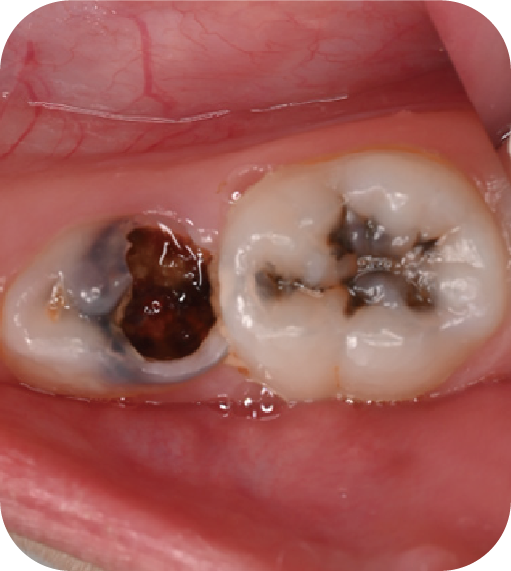

后磨牙,也就是大牙咬合面上凹凸不平的裂隙,這就是“窩溝”。窩溝有很多形狀,有的是狹長的裂隙形狀,還有的在牙齒深處又會分成幾條小溝。這些地方用牙刷很難深入清潔,于是就成了衛(wèi)生死角,細菌特別喜歡在里面生存,不斷產(chǎn)酸腐蝕牙齒,蛀牙就這樣產(chǎn)生了。如果我們用窩溝封閉把這些衛(wèi)生死角封起來,那既可以杜絕食物和細菌進入窩溝內,也可以讓窩溝處的清潔變得更簡單,這就是做窩溝封閉的目的。同時它也是世界衛(wèi)生組織、國家衛(wèi)健委都推薦的防齲方法。